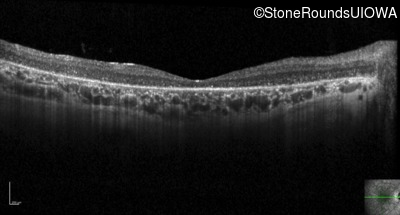

Optical Coherence Tomography - Left - 10/180 sc

Exemplar / OCT Stack